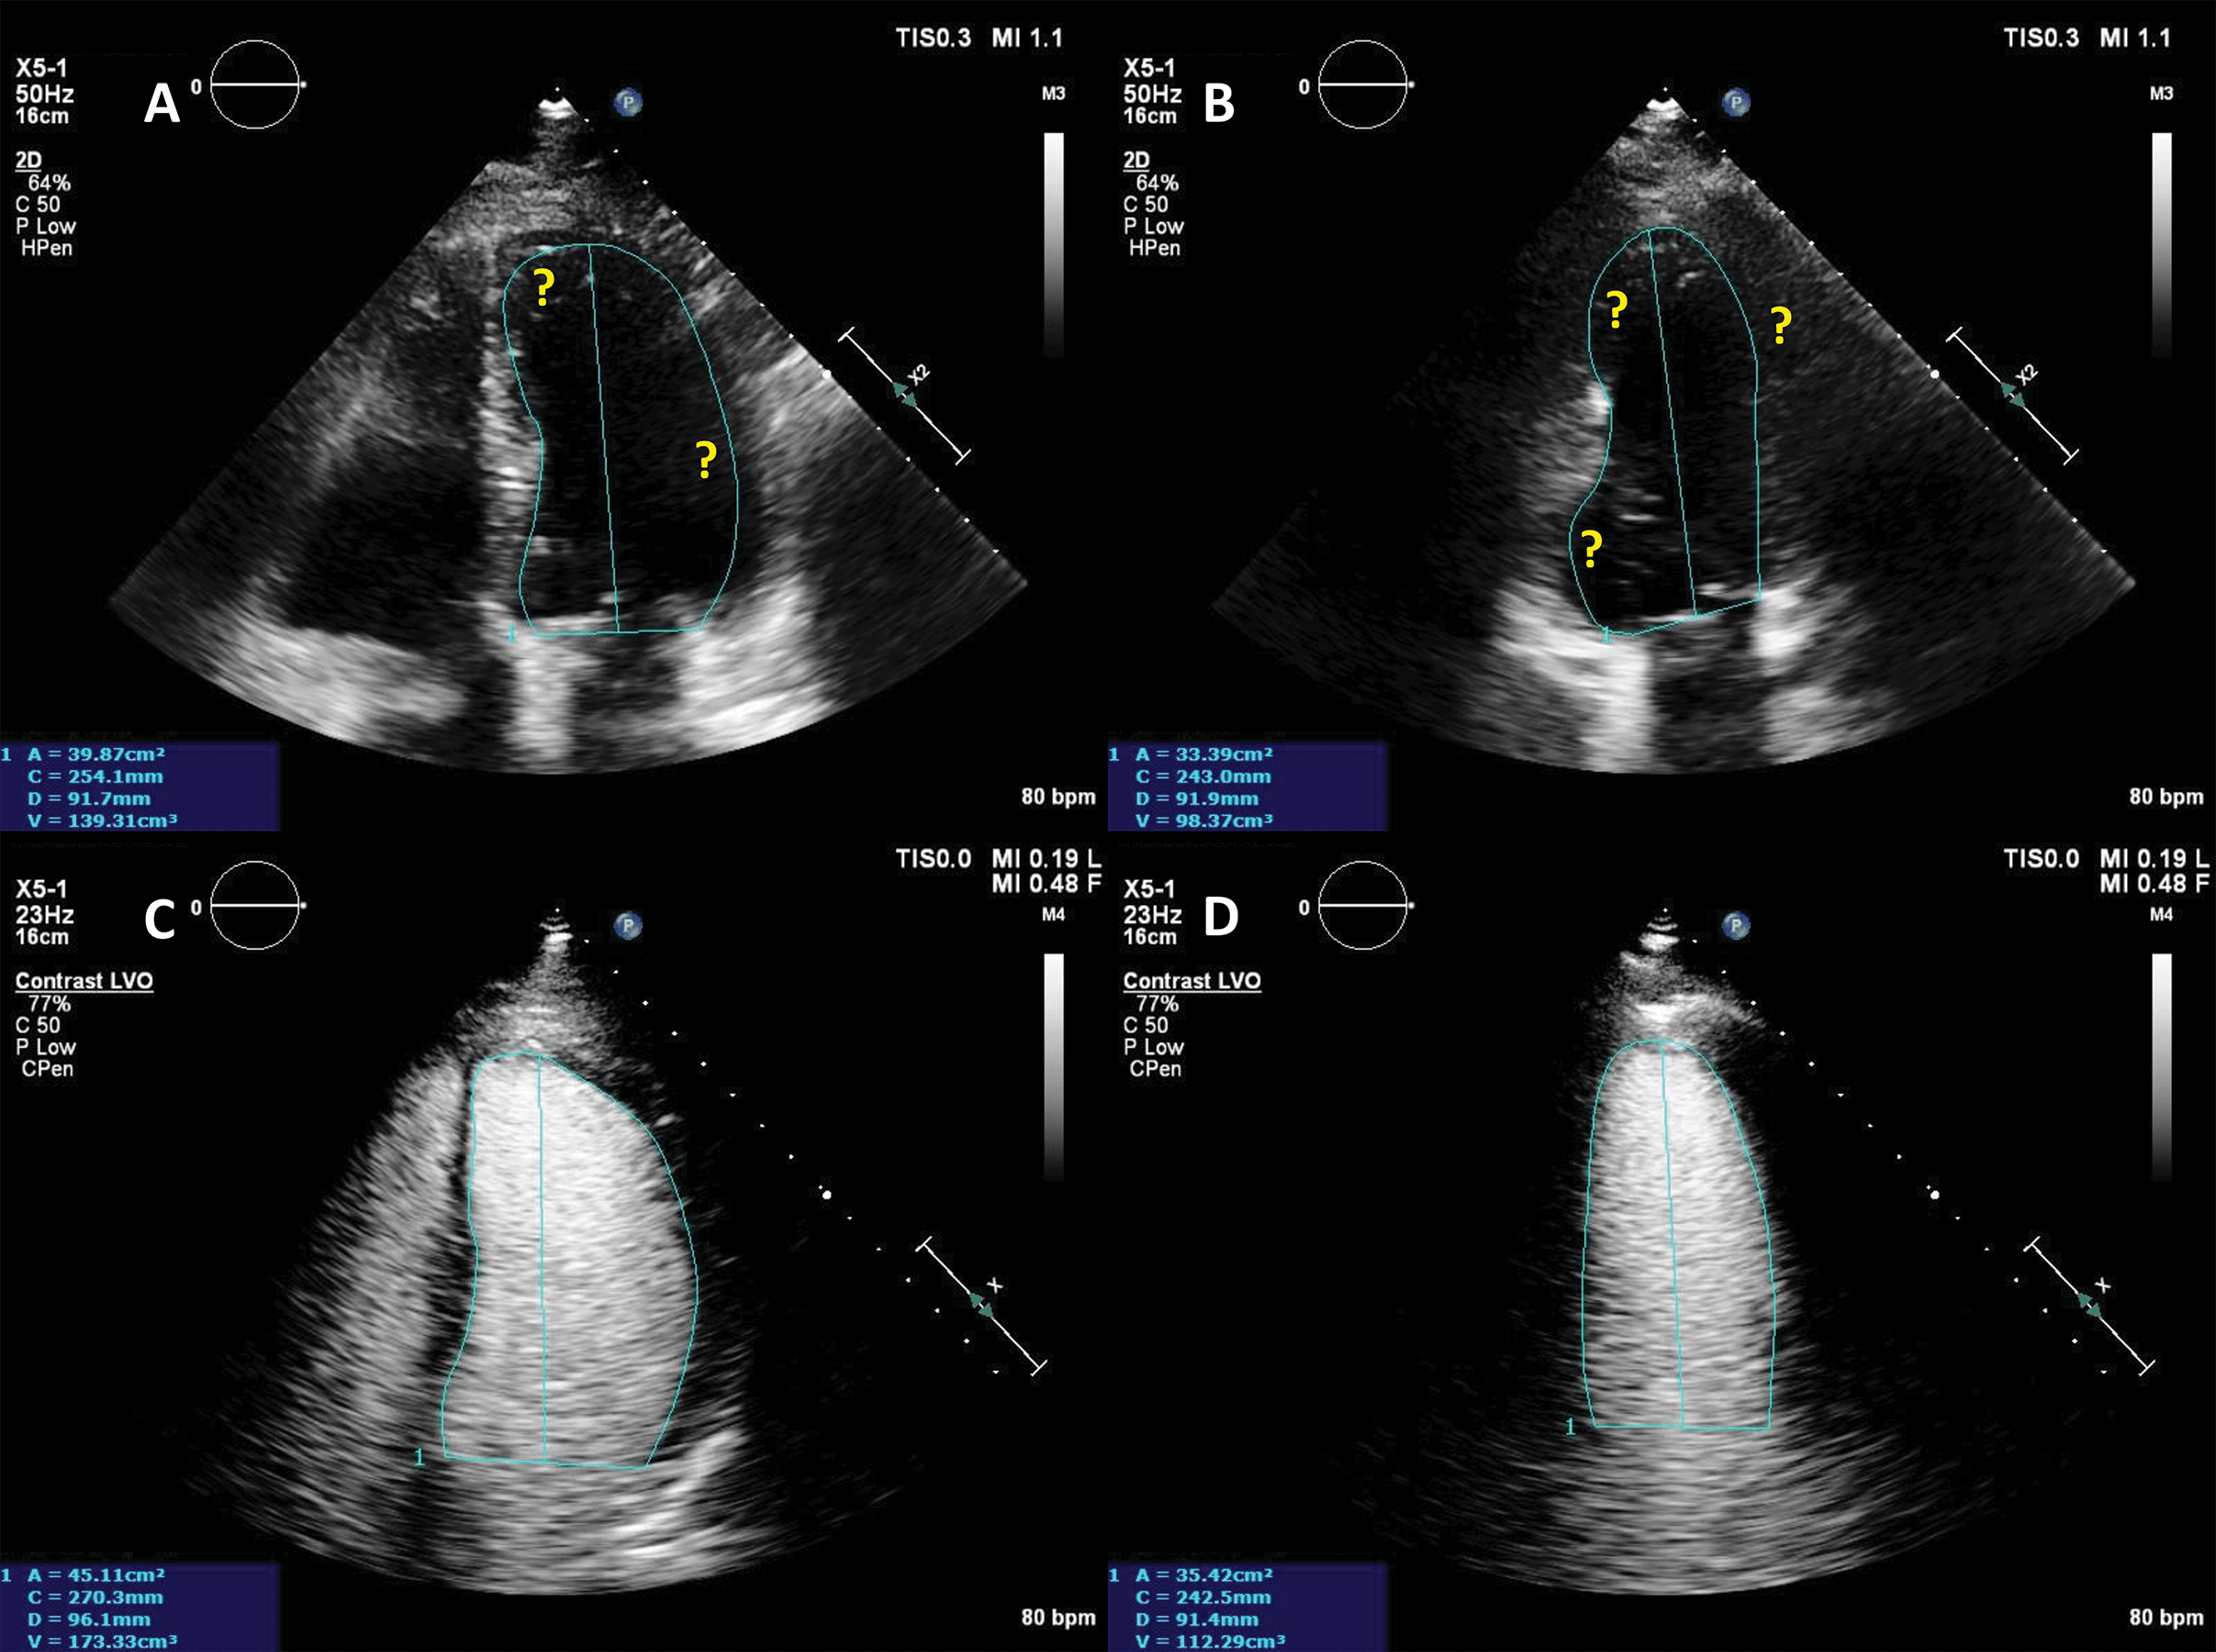

By using UEA, enhanced echocardiographic measurements of LV volumes and ejection fraction are very close to the reference cardiac magnetic resonance (CMR) values [11, 12], and significantly less variable as compared to unenhanced imaging, even if baseline images are of good quality [18]. This significant difference in quality, information and accuracy leads to a clinical impact on diagnosis and management [6, 19, 20]. Echocardiographic estimates of LV volume tend to be larger when using LVO, mainly because it aids the exclusion of trabeculae (Fig. 3), making the measurements closer to their CMR counterparts [13].

Fig. 3.Ejection fraction (EF) estimation. (A,B) Non-enhanced ultrasound images. The endocardium is not clearly visible in several segments (question marks), making the volumes difficult to assess. (C,D) Contrast-enhanced images. The endocardial border is clearly defined, allowing for a biplane volume estimation. Moreover, the LV end-diastolic volumes in contrast-enhanced images is notably larger than the one on the non-enhanced images, probably because of a combination of insufficient image quality on native images, and exclusion of trabeculae and papillary muscles on contrast images. Source: personal collection.